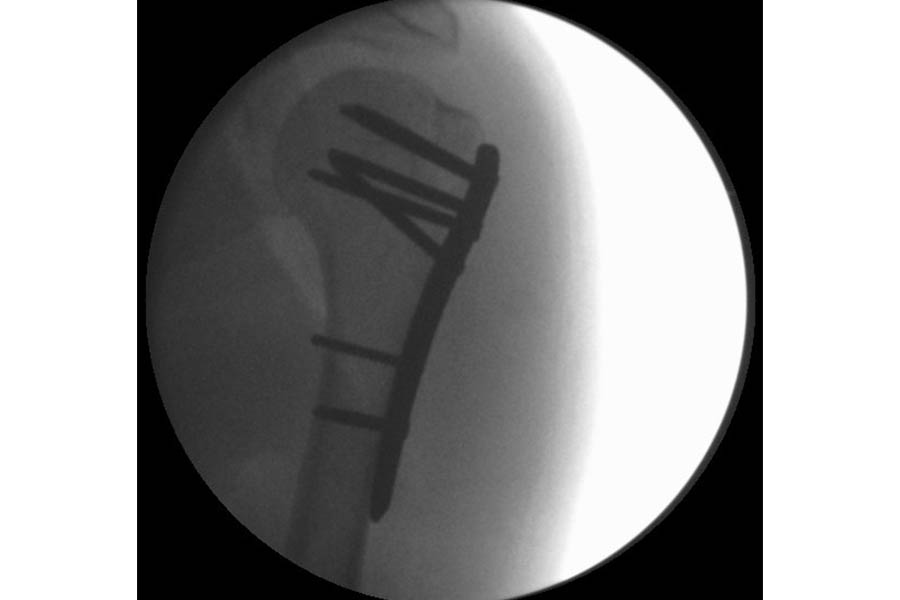

Trauma

Case 1